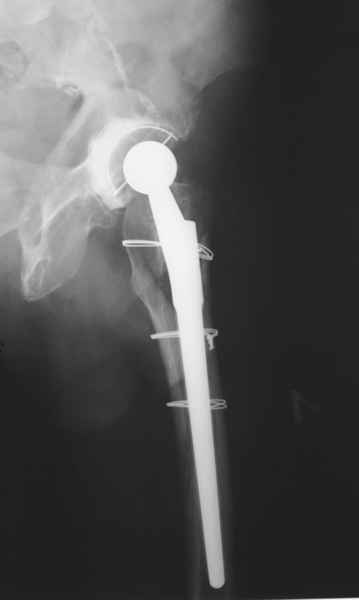

Уважаемые коллеги, продолжая дискуссию, начатую на "Вреденовских чтениях", хочу сказать, что принципиально сущестует два возможных варианта лечения.

2. Применение ножки дистальной фиксации, мы отдаем предпочтение ножке Вагнера с фиксацией проксимального отдела на ножке. Более травматичное вмешательство, но при стабильной фиксации ножки реабилитация идет в обычном режиме.

Хочется показать два подобных случая, П-ка З. 72 лет и п-т Г. 80 лет. Сразу принимаю замечание, что это были ножки цементной фиксации, просто под руками не было бесцементника.